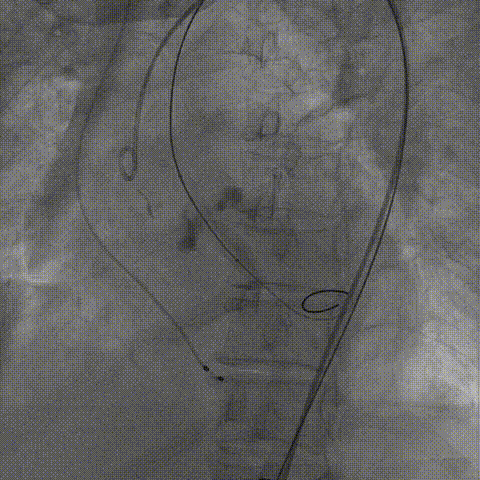

瓣膜最终造影

手术使用Z-Med 20mm球囊预扩两次,植入AV23 TaurusNXT主动脉瓣,Snare圈套器协助输送系统过弓、过瓣,120次/分起搏频率下,在左右重合位影像下释放瓣膜达到工作位,造影显示位置偏深,完全回收两次后释放达工作位,造影显示位置仍然不理想,之后第三次使用部分回收,精准释放瓣膜,之后使用Z-Med 20mm球囊后扩张两次。术后即刻超声心动图评估显示瓣膜位置良好,微量瓣周漏,主动脉瓣口峰值流速为1.90m/s,平均跨瓣压差为8mmHg,有效瓣口面积 1.60cm²,血流动力学指标理想。